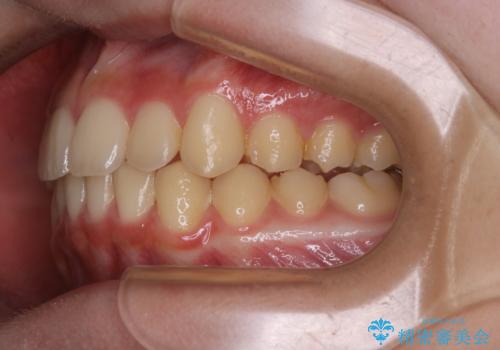

非抜歯で劇的に出っ歯を改善!インビザラインとカリエールの組み合わせ治療

- 患者様、出っ歯のお悩みで来院されました。

骨格の分析を行ったところ上顎も出てはいるのですが、下顎が引っ込んでいる状態であるということがわかりました。

よって上顎の歯を抜いて治療をするのではなく、カリエールという器具を使用して下顎を前に引っ張り出しながら上顎を引っ込めるという治療を行うことにしました。